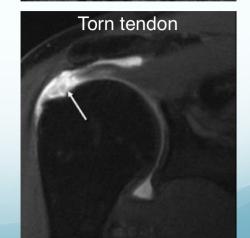

Section 3: Shoulder Pathology & Examination

Questions 17-20: Shoulder Injuries and Tests

Clinical Scenario: 45 years old male fell from height and landed on his shoulder and presented to your clinic with painful shoulder.

Q17: What is the following test name and what does it test?

Apprehension test for anterior shoulder instability

Q18: What is the following test name and what does it test?

Empty can test for Supraspinatus power